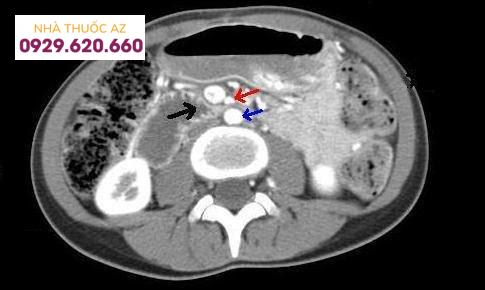

CT bụng và vùng chậu cho thấy: tá tràng bị chèn ép (mũi tên đen) giữa động mạch mạc treo tràng trên (mũi tên màu đỏ) và động mạch chủ bụng (mũi tên màu xanh).